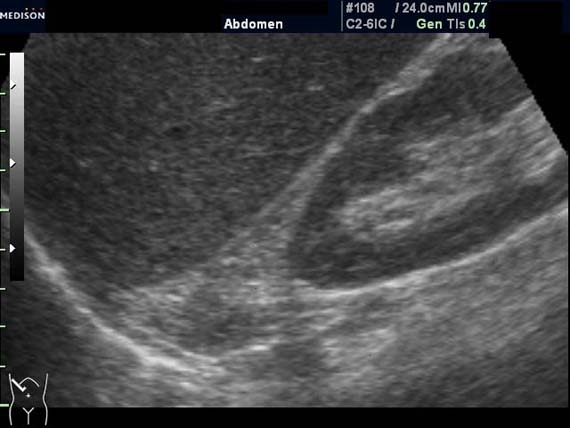

Женщина 50 лет. Жалоб нет. Обследование перед поездкой в санаторий по поводу дисфункции гепатобилиарной системы.

Случайная находка в нижней трети левой почки (не в полюсе, а по задне-медиальной поверхности).

ПО УЗ-семиотике образование соответствует ангиомиолипоме (AML). По правилам в таких случаях необходимо выполнить КТ, доказать преимущественно жировой состав опухоли, затем проводить УЗ-наблюдение.

Согласен. Именно с таким диагнозом (ангиомиолипома) отправил на КТ. Особенностью случая ИМХО является заметный "выход" образования за контур почки (на 2/3 объема).

При ультрасонографии ангиомиолипома выглядит как округлое образование без капсулы с однородной внутренней эхоструктурой и четкими контурами; эхогенность ее чаще всего равна или чуть выше эхогенности перинефральной клетчатки [7]. Значительно реже эхогенность ангиомиолипом может быть равна эхогенности почечной паренхимы; такие опухоли состоят почти полностью из гладкомышечной ткани [8]. Иногда позади ангиомиолипомы может определяться слабая акустическая тень.